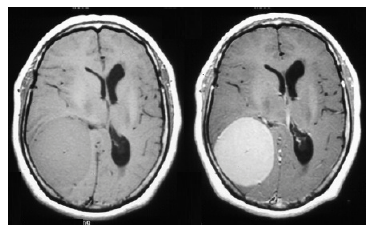

Uma paciente de 57 anos de idade, proveniente do interior de São Paulo, refere cefaleia holocraniana há cerca de quatro anos. Há três meses, houve uma piora da cefaleia, acompanhada de episódios de vômitos e dificuldade para caminhar. Ao exame físico, apresentava fundo de olho com edema de papila bilateral e hemiparesia no hemicorpo esquerdo.

Realizou investigação complementar com exames de ressonância magnética sem e com contraste, que evidenciaram as imagens abaixo.

RM T1 sem contraste RM T1 com contraste

Com base nesse caso hipotético, assinale a alternativa correta.